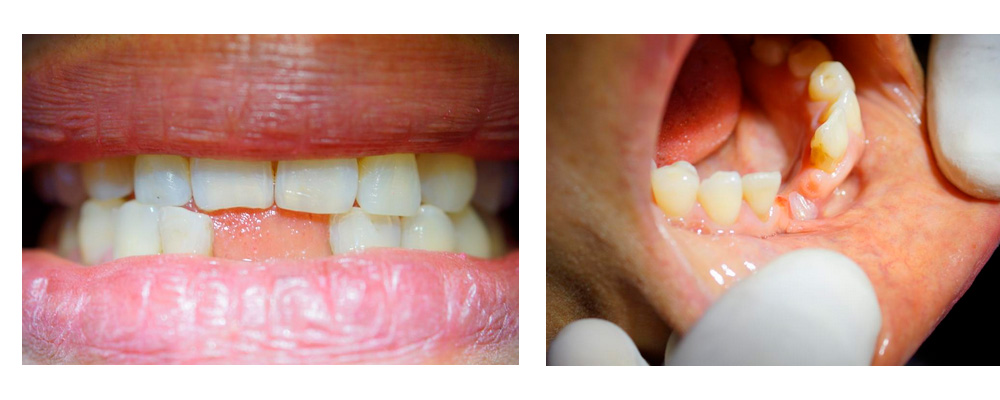

Paciente femenino de 44 años de edad; aparentemente sana solicita atención dental por perdida de órganos dentarios 31 y 41 a la edad de 20 años en accidente casero; se practica historia clínica y la firma, acepta el tratamiento y otorga consentimiento con publicación de su caso clínico. En la exploración no presenta patologías bucales y hay ausencia dental de los dos órganos dentales centrales inferiores (fig. 1); se observa espacio interdental entre los laterales inferiores de 7.3 mm y una reabsorción completa del reborde mandibular (fig. 2).

La figura 10 muestra la sonrisa al culminar el tratamiento y se puede comparar con la figura 1 al inicio del tratamiento. Se dictamina un pronóstico favorable.